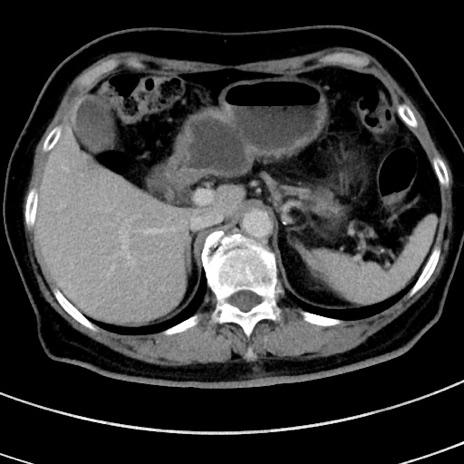

冠状断像

【症例】 60歳代女性

【主訴】むかつき、みぞおちの痛み

【現病歴】3日前よりむかつきがあり、食事がとれない。

【既往歴】糖尿病

【身体所見】発熱なし、心窩部圧痛軽度あるも、腹膜刺激症状なし。

【データ】WBC 7400、CRP 1.92